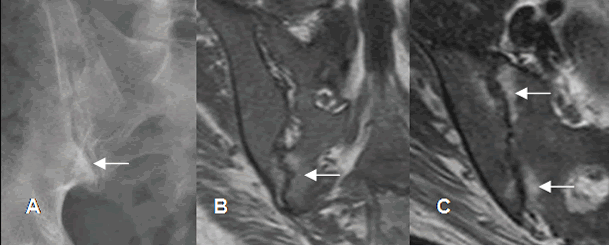

Fig 13 A. Sacroileitis por enfermedad de Crohn.

A: TAC axial. Engrosamiento y captación de la pared, en una asa de intestino delgado, por enfermedad de Crohn. B: RM coronal en T1 y C: RM axial en STIR. Lesiones hipointensas en T1 e hiperintensas en STIR, sobre ambas sacroiliacas, por inflamación aguda.